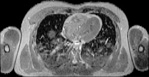

Visible Human male: Sectio transversalis 1457

CT

NMR

Pd                          / T2 \                         T1